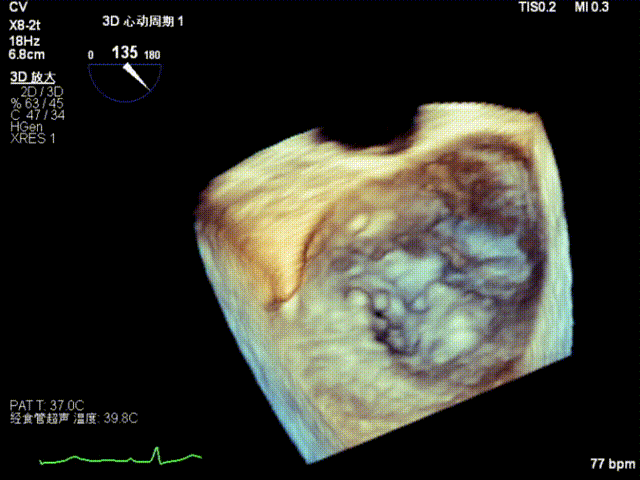

术后超声

最终在A3P2位置夹合,前叶夹合量10mm,后叶夹合量8mm,剩余瓣口面积3.45cm²,平均跨瓣压差2mmHg,反流基本消除。